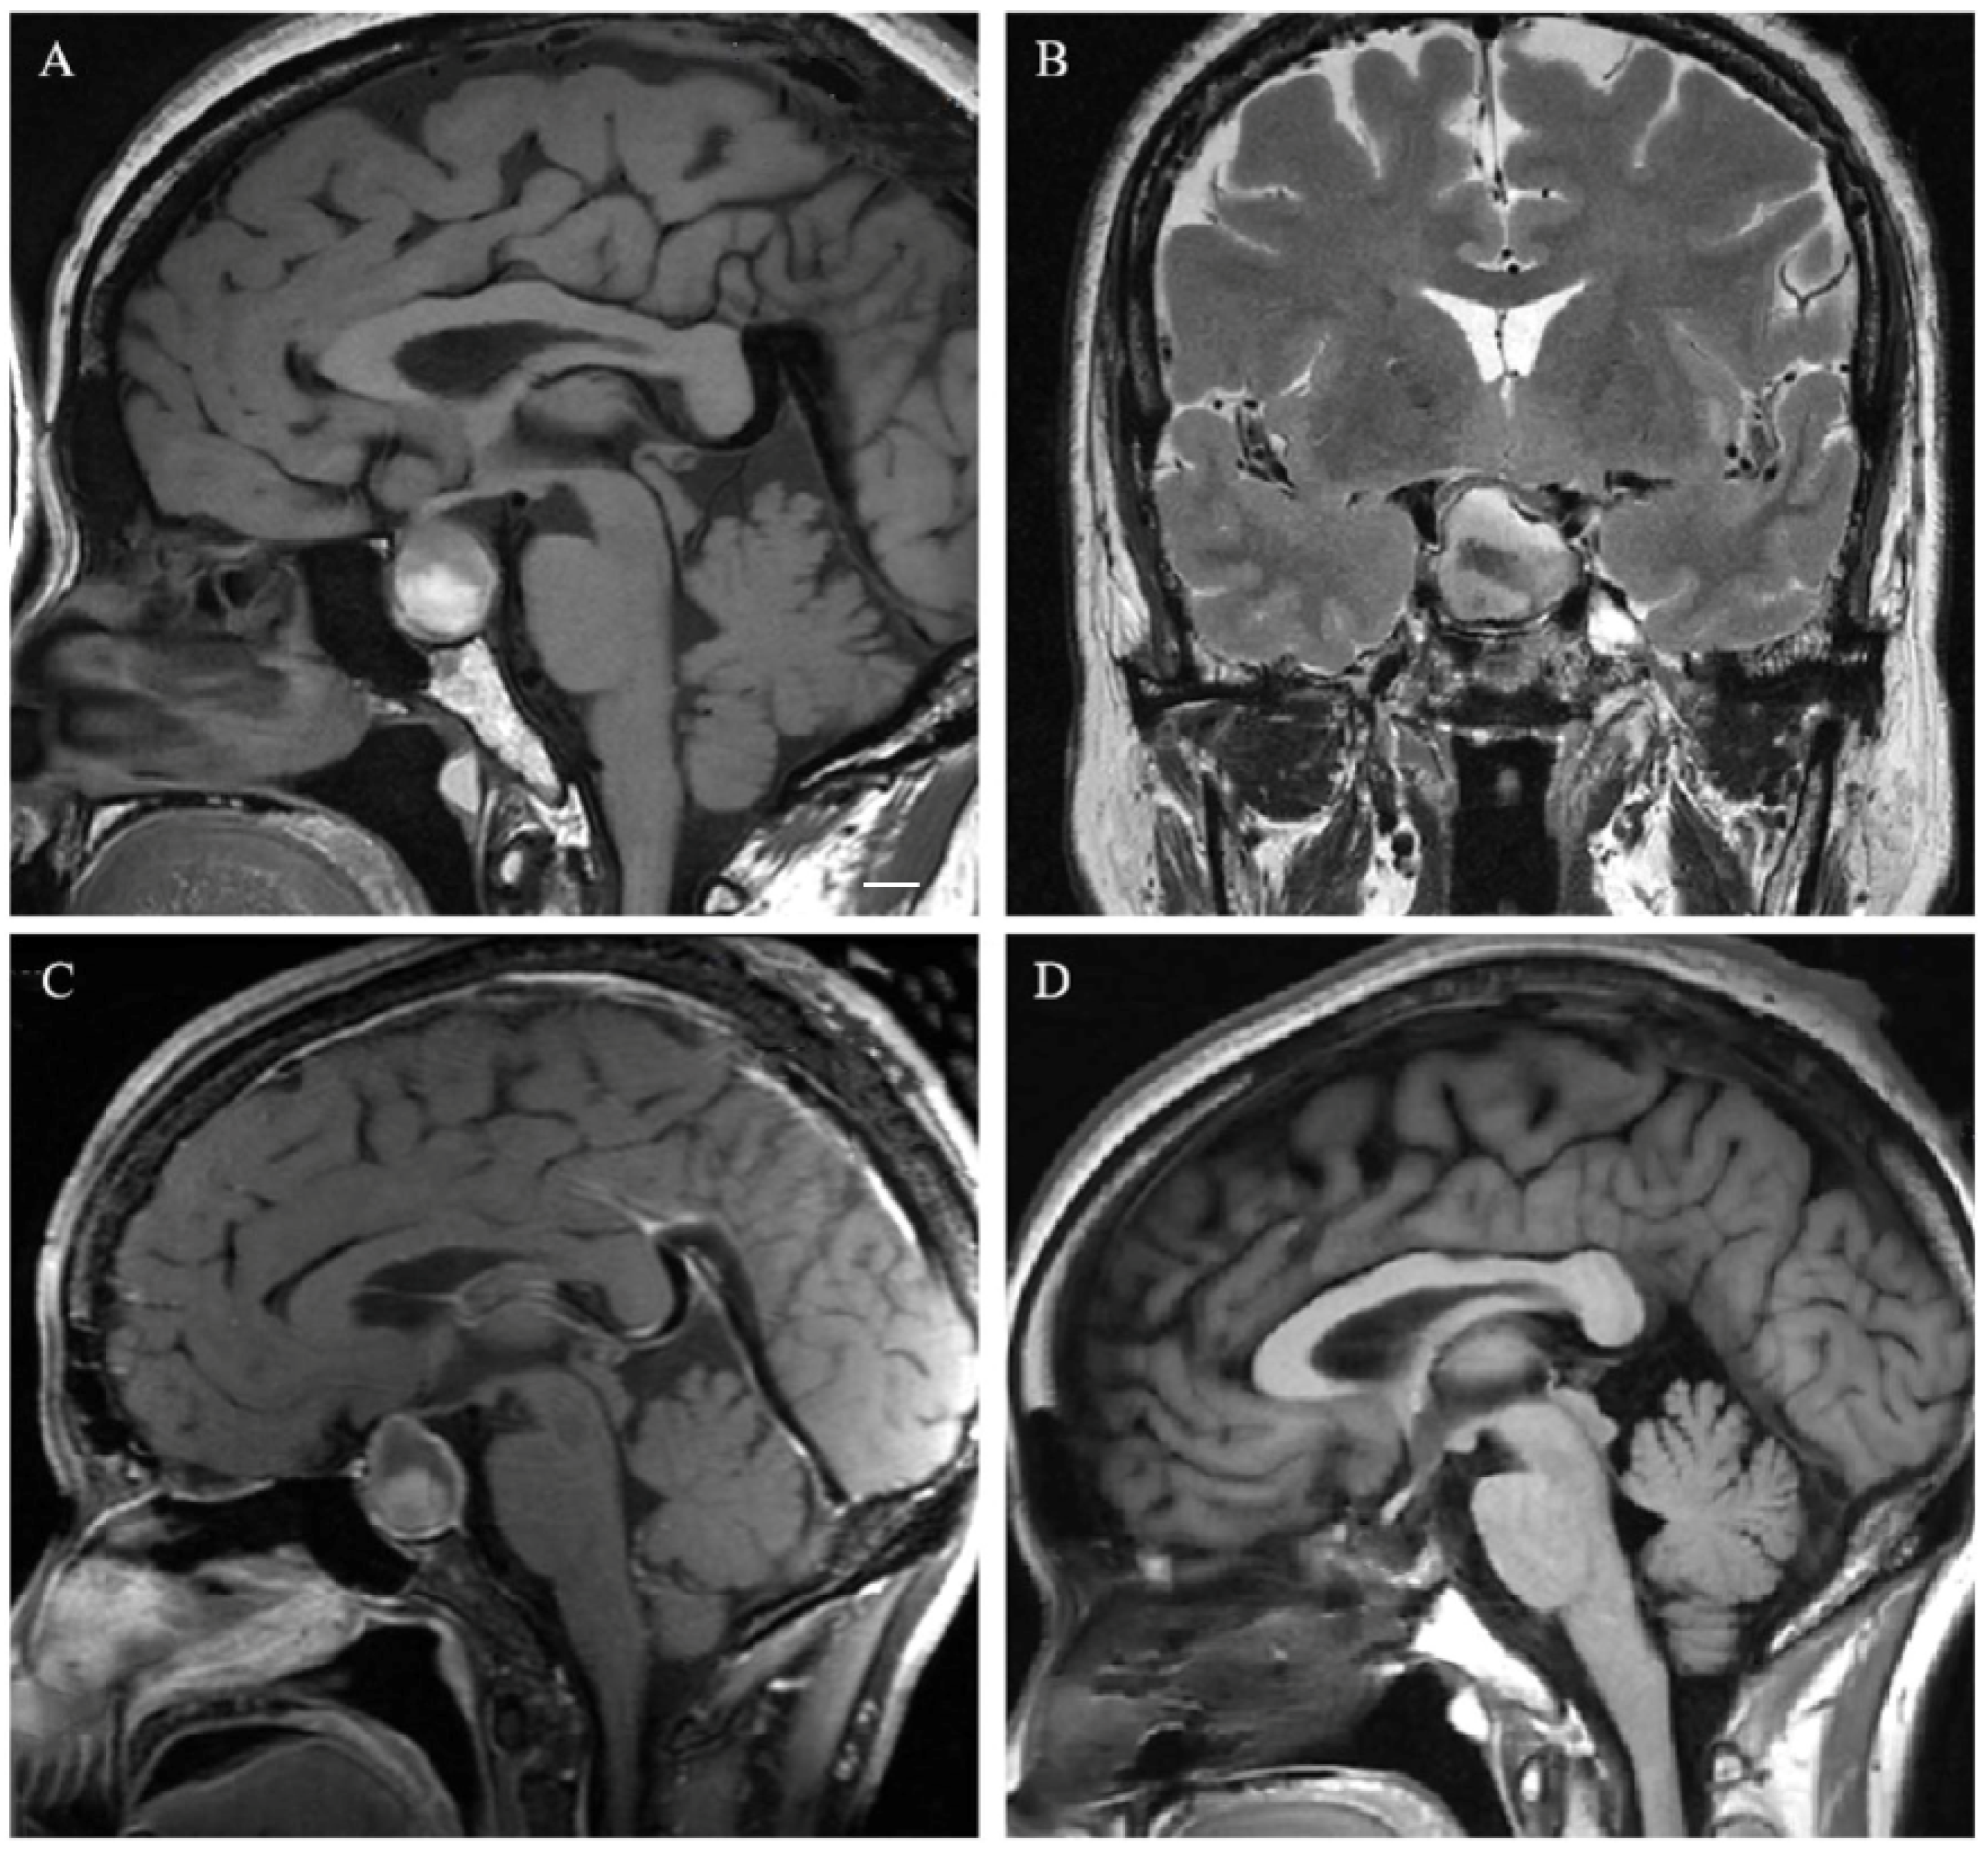

2.3. Neuroradiological Evaluation

3.2. Neuroradiological Features